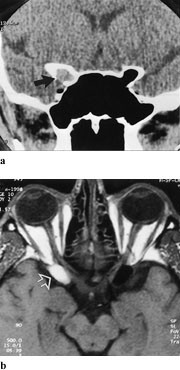

Lymfomer involverer oftest øvre del av orbita, inklusive øvre rette øyemuskel, og presser øyet nedover (fig 8 a, b). Det er svært vanskelig å differensiere røntgenologisk mellom lymfoid lesjon og lymfom i orbita, men der er også overlapping mellom de forskjellige typer histologisk. Karakteristisk er det, som også ved myositt, at muskelsenen er affisert. Både på MR og CT sees lymfomene som homogene, velavgrensede strukturer.

Kapillære hemiangiomer kan markere seg som blågrå misfarging av huden. CT viser isodens, lobulær masse med markert kontrastoppladning (fig 9 a, b). Venøse malformasjoner kan øke i størrelse ved forskjellig aktiviteter som f.eks. gråt eller andre manøvrer som forårsaker venøs trykkøkning. Angiografi er ikke godt egnet til å påvise slike malformasjoner. Valsalvas manøver utført under spiral-CT-undersøkelse kan demonstrere den klassiske økningen av lesjonens størrelse hvis pasienten samarbeider og er i stand å holde pusten i 20 – 25 sekunder. Slike lesjoner kan imidlertid best påvises ved dopplerfargestrømsultralydundersøkelse.